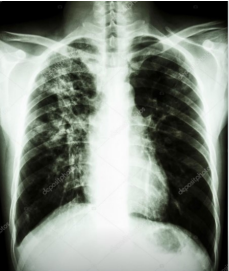

Paciente comparece queixando febre, tosse produtiva com expectoração mucopurulenta de início há 1 semana com eliminação de sangue no escarro. Questionado, afirma passado de tratamento para tuberculose. Realizada radiografia de tórax (abaixo).

A melhor conduta terapêutica para este paciente neste momento é